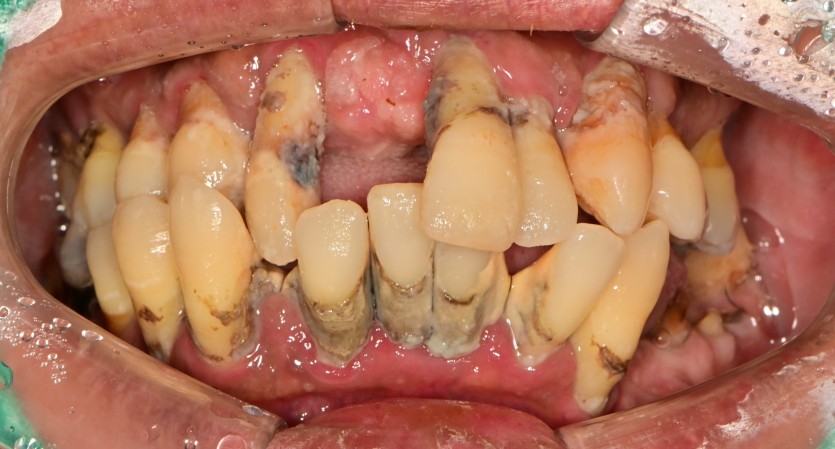

전체 임플란트 증례입니다.

18개의 임플란트로 완성하였습니다.